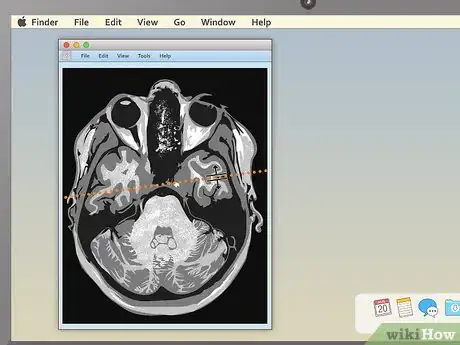

4Use the section-cut line to see where cross-sections are located. If you display a cross-sectional image along with a sagittal or coronal image, you may see a section-cut line on the second image. This will be a straight line running through the image, but it may not be present on all MRIs. If your image does have one, this shows where on the second image the cross section is located. You should be able to move the section cut line toward the center, right or left of the image. This will change the larger layout image to show the body from the new direction of the scan.

- The section-cut line on the layout picture also shows the direction that the image was taken from. For example, if your MRI were a picture of an everyday object, like a tree, the section cut line might show you if the picture was taken from above in a plane, from a second-story window, or from the ground.